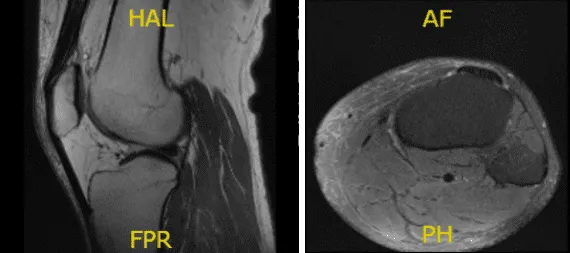

Resonancia magnética realizada y revisada por el médico. Se demostró que la rodilla izquierda del paciente está intacta en el menisco medial y lateral y no presenta lesión ósea aguda, pero sí un pequeño derrame articular. La troclea central presenta una fisura condral focal y fibrilación en la porción media del cóndilo femoral medial.

Sin embargo, la rodilla derecha del paciente previo, meniscectomía lateral parcial con diminuto cuerno anterior con una re-rotura en el cuerpo del menisco lateral. Debido a la extrusión del cuerpo, el menisco lateral causa osteoartritis tricompartmental demasiado leve a moderada con un derrame articular pequeño.